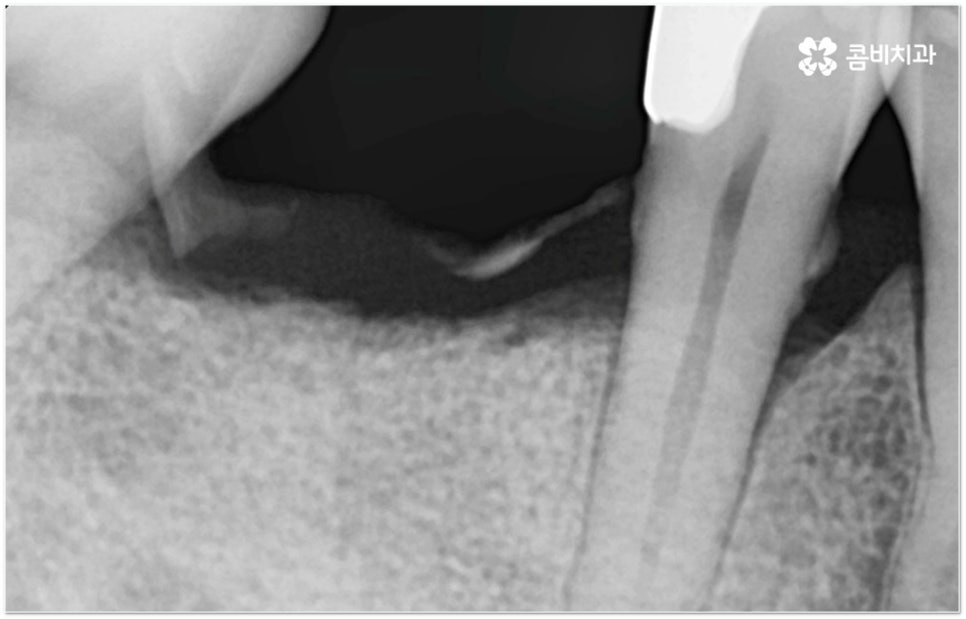

그러나 임플란트는 잇몸뼈에 직접 심어서 고정시키는 방식인 만큼 만약 환자분의 잇몸뼈가 부족하거나 치아가 빠진 후 오랜 시간이 지나 이미 잇몸뼈 소실이 상당 부분 이루어진 상태라고 한다면 먼저 골이식을 통해 이를 보충한 후 식립을 진행하는 뼈이식임플란트 방식을 이용할 필요가 있어요. 골이식 과정은 바탕이 되는 잇몸뼈의 밀도나 높이, 두께가 부족한 부분에 이식 재료를 심어주어 뼈를 재건해 주는 것인데 충분한 시간을 두고 무리하지 않게 진행하는 것이 뼈이식임플란트 수술의 성공률 및 안정적인 지속성을 높일 수 있는 방법이 될 거예요.

뼈이식임플란트 가 필요한지 살펴볼 때 3D CT 촬영과 같은 정밀 진단을 통해서 환자분의 잇몸뼈 두께 등 치조골 상태 뿐 만 아니라 구강 구조, 치아 및 잇몸 상태, 신경관 위치, 상악동까지의 거리 등을 꼼꼼하게 확인하여 치료 계획을 세우고 필요하다면 구강 질환에 대한 치료나 상악동 거상술 등을 선행하며 잇몸뼈 부족에 대해서도 골이식 과정을 먼저 진행하게 되는데요, 이러한 뼈이식임플란트 시술은 상당히 고난도의 복잡한 치과 진료인 만큼 관련 임상 경험이 풍부한 의료진과 함께 하는 것이 굉장히 중요하며 또한 수술 후 관리 면에서도 더욱 신경을 써 주시길 당부드리고 있어요.